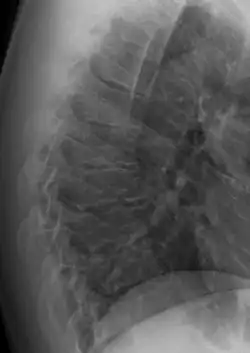

Scheuermann's disease

| Scheuermann's disease on lateral Xray of the T spine | |

Scheuermann's disease is a skeletal disorder.[3] It describes a condition where the vertebrae grow unevenly with respect to the sagittal plane; that is, the posterior angle is often greater than the anterior. This uneven growth results in the signature "wedging" shape of the vertebrae, causing kyphosis. It is named after Danish surgeon Holger Scheuermann.[4][5][6]

Scheuermann's disease is considered to be a form of osteochondrosis of the spine. It typically develops during adolescence and presents a significantly worse deformity than postural kyphosis. Patients with Scheuermann’s kyphosis cannot consciously correct their posture. The apex of their curve, located in the thoracic vertebrae, is quite rigid.

In addition to the pain associated with Scheuermann's disease, many individuals with the disorder have loss of vertebral height, and depending on where the apex of the curve is, may have a visual 'hunchback' or 'roundback'. It has been reported that curves in the lower thoracic region cause more pain, whereas curves in the upper region present a more visual deformity. Nevertheless, it is typically pain or cosmetic reasons that prompt sufferers to seek help for their condition. In studies, kyphosis is better characterized for the thoracic spine than for the lumbar spine.[7][8]

The seventh and tenth thoracic vertebrae are most commonly affected. It causes backache and spinal curvature. In very serious cases it may cause internal problems and spinal cord damage. The curvature of the back decreases height, thus putting pressure on internal organs, wearing them out more quickly than the natural aging process; surgical procedures are almost always recommended in this case.

Diagnosis is typically by medical imaging. The degree of kyphosis can be measured by Cobb's angle and sagittal balance.